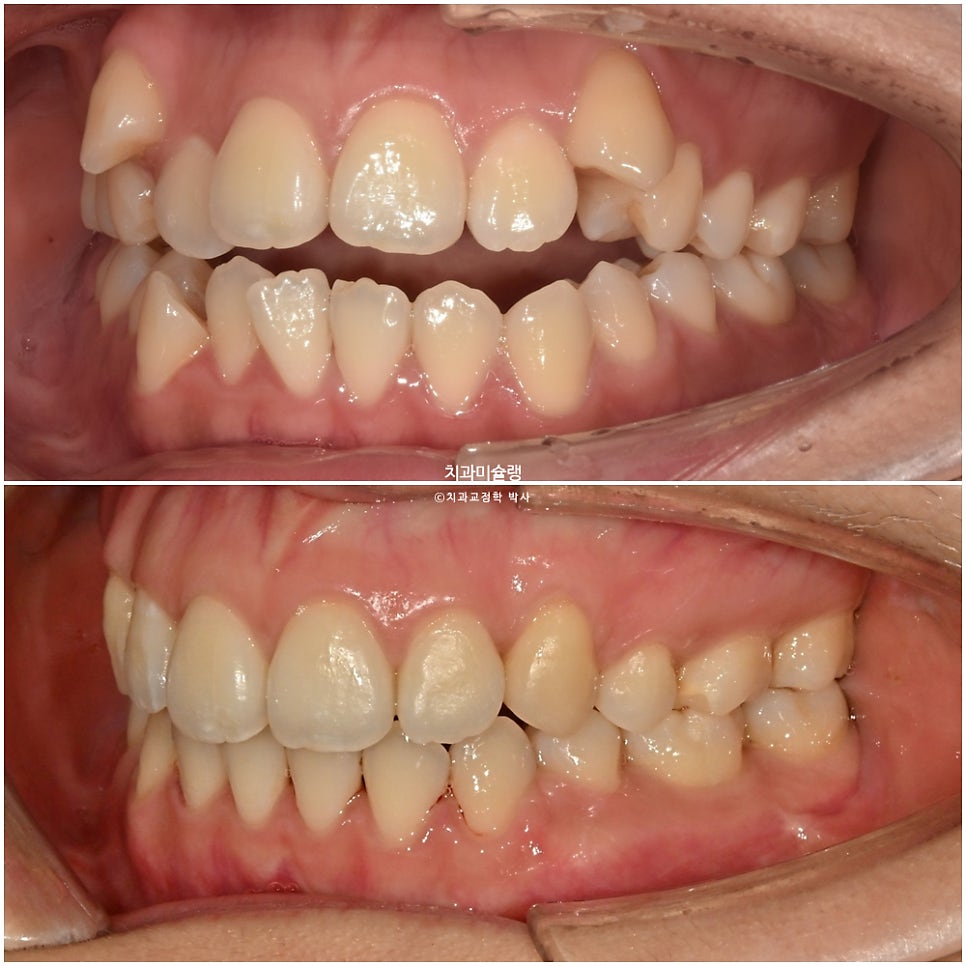

어금니 교합관계는 2급 입니다.

중심선은 잘 맞으며 송곳니는 제자리로 잘 내려왔죠. 개방교합도 완벽히 개선되었습니다.

어금니 교합은 이미 좋습니다.

어금니 교합은 좋으며 1급 교합관계를 보입니다.

치료 결과 비교

이제 전후비교 보겠습니다.

송곳니 덧니 때문에 윗입술 양측이 들려있던 부분이 개선되었습니다.

아랫입술은 소량 뒤로 들어갔고 윗입술은 거의 처음 그대로 유지되었습니다.

2년 5개월간의 옆모습 엑스레이 변화는 이러합니다. 앞니 각도는 적절하며 발치교정임에도 불구하고 비순각 및 입매는 잘 유지되었습니다.